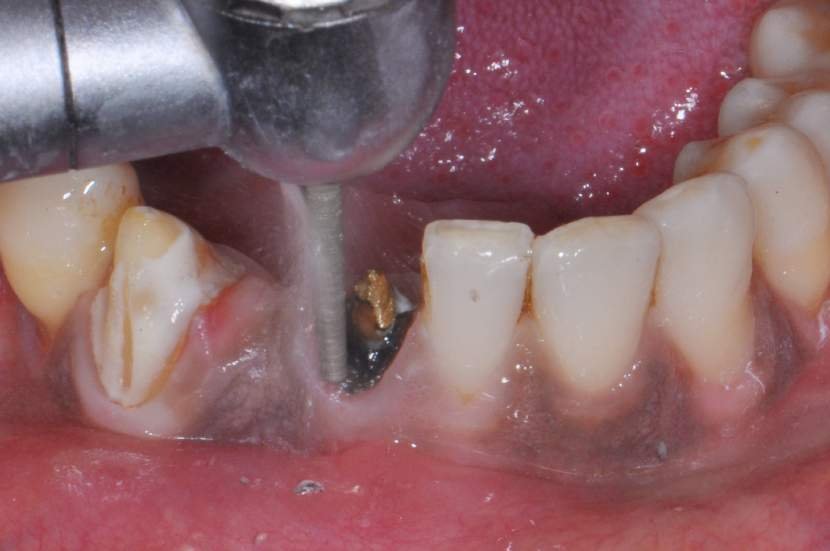

TÉCNICA CIRÚRGICA

O procedimento cirúrgico para os implantes Slim segue um protocolo semelhante como outros implantes, porém muito simplificado. Normalmente utilizase a técnica anestésica infiltrativa. Um retalho mucoperiosteal deve ser rebatido para uma observação direta do rebordo ósseo disponível. No entanto, quando o tecido queratinizado e o volume ósseo abundantes estiverem presentes, uma cirurgia flapless é muitas vezes o protocolo cirúrgico de escolha.2

Para instalação de implantes de Ø 2.5mm é necessário apenas a utilização da fresa lança diâmetro de 2.0 mm. E para instalação de implantes de 3.0 mm utilização da fresa lança diâmetro de 2.0 mm e opcionalmente a fresa Countersink Slim 3.0mm (em casos de osso tipo I ou tipo II). O implante tem o ápice cortante e espiras que facilitam sua instalação. Os implantes Slim se apresentam de 1 em 1 mm de comprimento de 7 a 13 mm, o que facilita muito a escolha dos tamanhos no momento do planejamento.

CASO CLÍNICO

Paciente com perda do incisivo central inferior do lado direito, utilizando uma prótese fixa em zircônia com estética e adaptação deficientes.